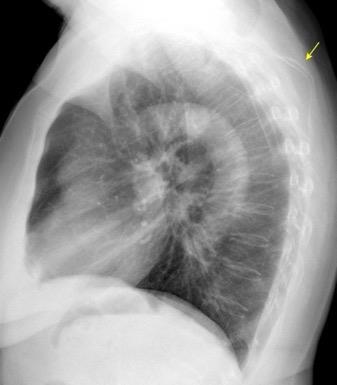

Densidad similar al músculo con estriaciones internas de grasa

Hallazgo incidental . Región infraescapular 2% de TC del tórax. Bilateral 60%.

Burt AM et al. Imaging review of lipomatous musculoskeletal lesions. SICOT J2017/ Murphey MD et al. From the archives of the AFIP: benign musculoskeletal lipomatous lesions. Radiographics. 2004